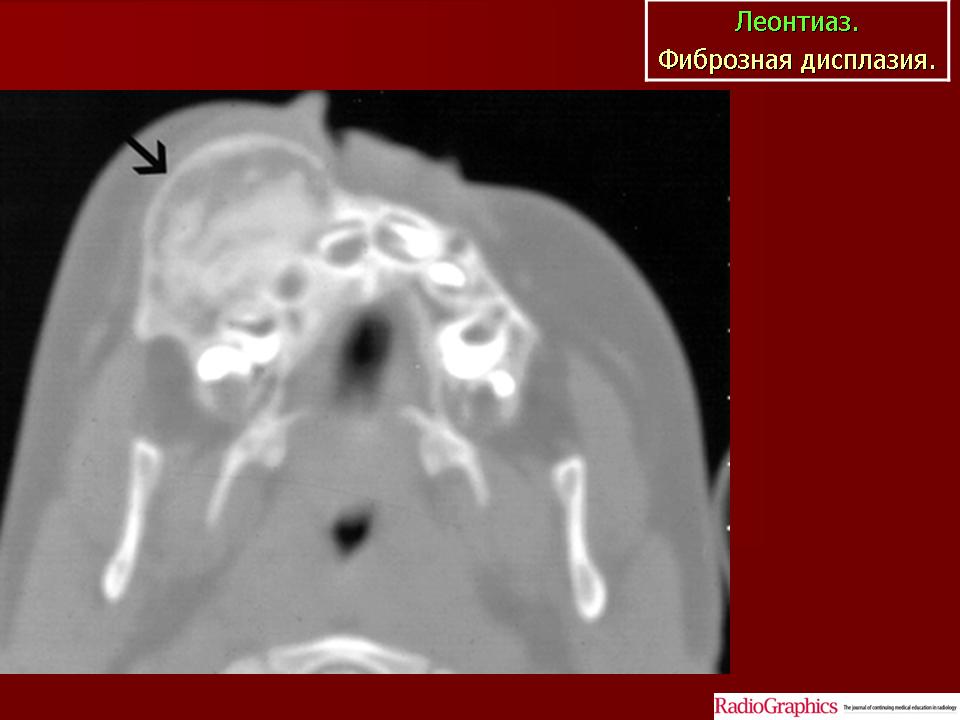

Костный леонтиаз.

Чаще всего при множественной форме фиброзной дисплазии поражены одновременно лобная и верхнечелюстные кости. Фиброзная дисплазия верхней челюсти в литературе получила название «костного леонтиаза», или «костной львиности». Всего описано около 140 наблюдений фиброзной дисплазии подобной локализации.

Она разрастается, занимая большой объем, кость принимает «вздутый» вид. При локализации в верхнечелюстной кости появляются асимметрия лица, выступание пораженной верхней челюсти, а при двустороннем поражении — «львиное» выражение лица.